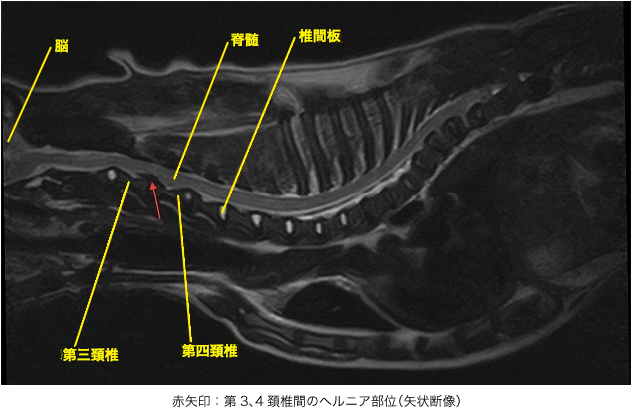

MRI検査では脳炎の所見は認められず、頚部において第3、4頚椎間の椎間板がヘルニアを起こし、左腹側から脊髄を圧迫していることが分かりました。以上のことから第3、4頚椎間の椎間板ヘルニアと診断しました。